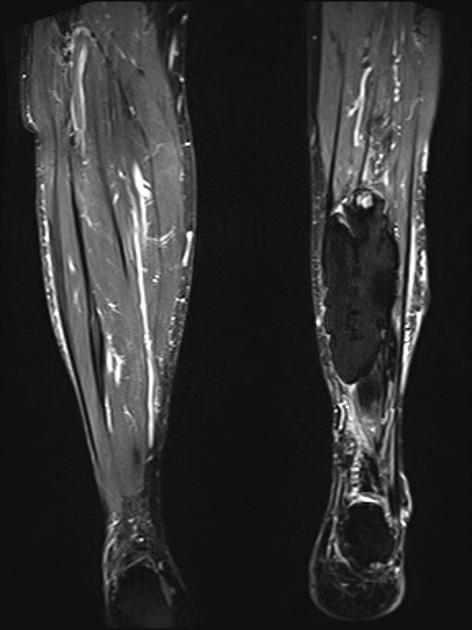

MRI may be used as a means of assessing the extent of the lesion. In the early phase, the lesion is isointense to muscle on the T-1 weighted images and hyperintense to muscle on T-2. As progressive ossification of the periphery occurs in the subacute phase, there will be the formation of a hypointense outer rim on the T-1 weighted images (3). Enhancement is present on the post-contrast images. With further maturation, the lesion becomes hypointense on both the T-1 and T-2 weighted sequences.

Figure 5 is a T-1 weighted image of an MO lesion in the left lower leg. It is fairly isointense to muscle on this image with a low signal periphery. Figure 6 is an accompanying STIR image, which demonstrates a fatty component and thus manifests a uniformly low signal.